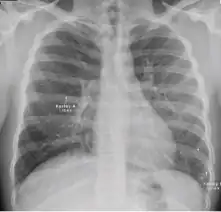

Chest x-ray showing nodule with margins that are indistinct or poorly defined (tree-in-bud sign) in post-primary pulmonary TB.